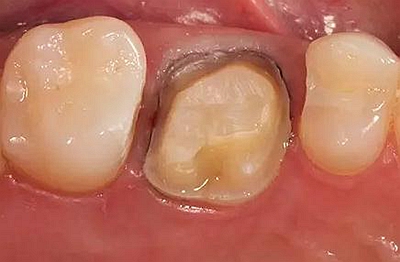

步骤3

牙体制备完成后的牙合面观

牙合面观察牙体预备之后的情况。

轴壁按要求预留0.8 mm 宽度。